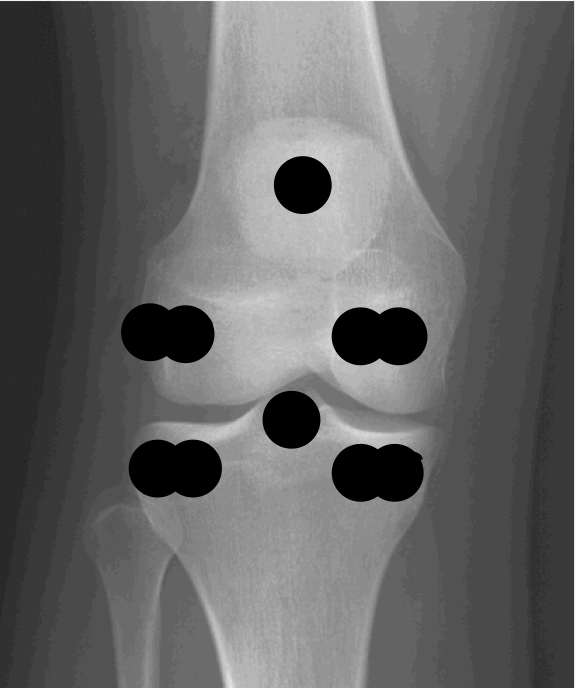

Label: